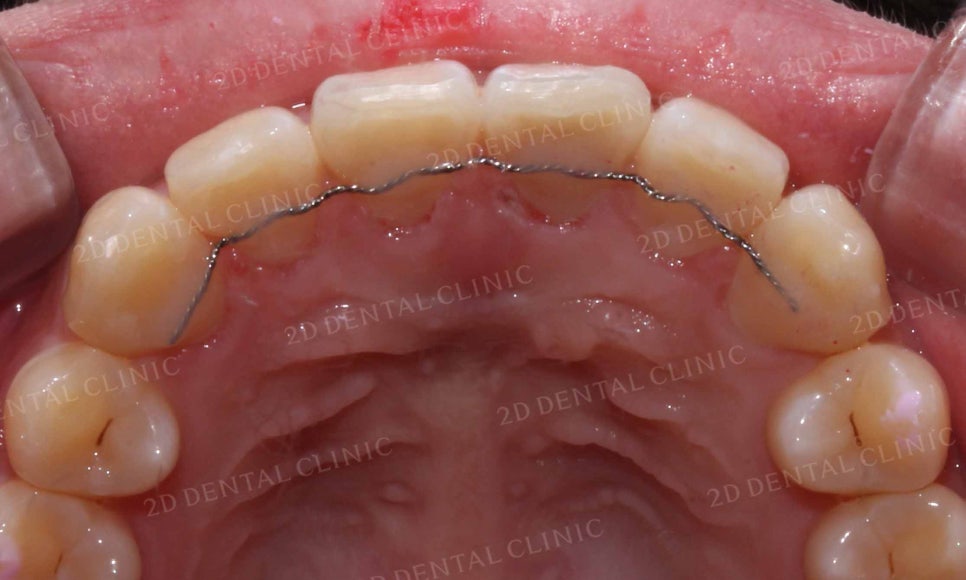

윗니의 치열을 보시면 앞니가

주변 치아들보다 바깥으로 뻗어져 있고

틀어짐도 심한 모습인데요,

흔히 토끼앞니 증상이 있으신 환자분들께서

앞니가 유난히 크다는 말씀을 하십니다.

그러나 이러한 치아의 크기차이는 치열이

흐트러짐으로 인해 발생하는 착시효과로

교정 후 정상적인 치열로 바뀌면

치아의 크기가 일정하게 보이게 됩니다.

아랫니의 안쪽 면을 보시면

윗니보다 치열의 틀어짐이 심하고

삐뚤삐뚤한 모습인데요,

치아의 겉면이 아닌 안쪽면에

교정장치를 부착하는 2D교정을 통해

치아의 틀어짐(총생)을 바로잡는 계획을 세웠습니다.